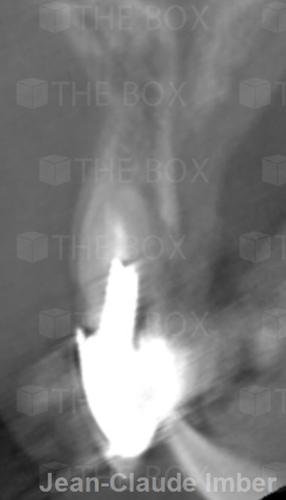

A new case was made public by Jean-Claude Imber check it out here.